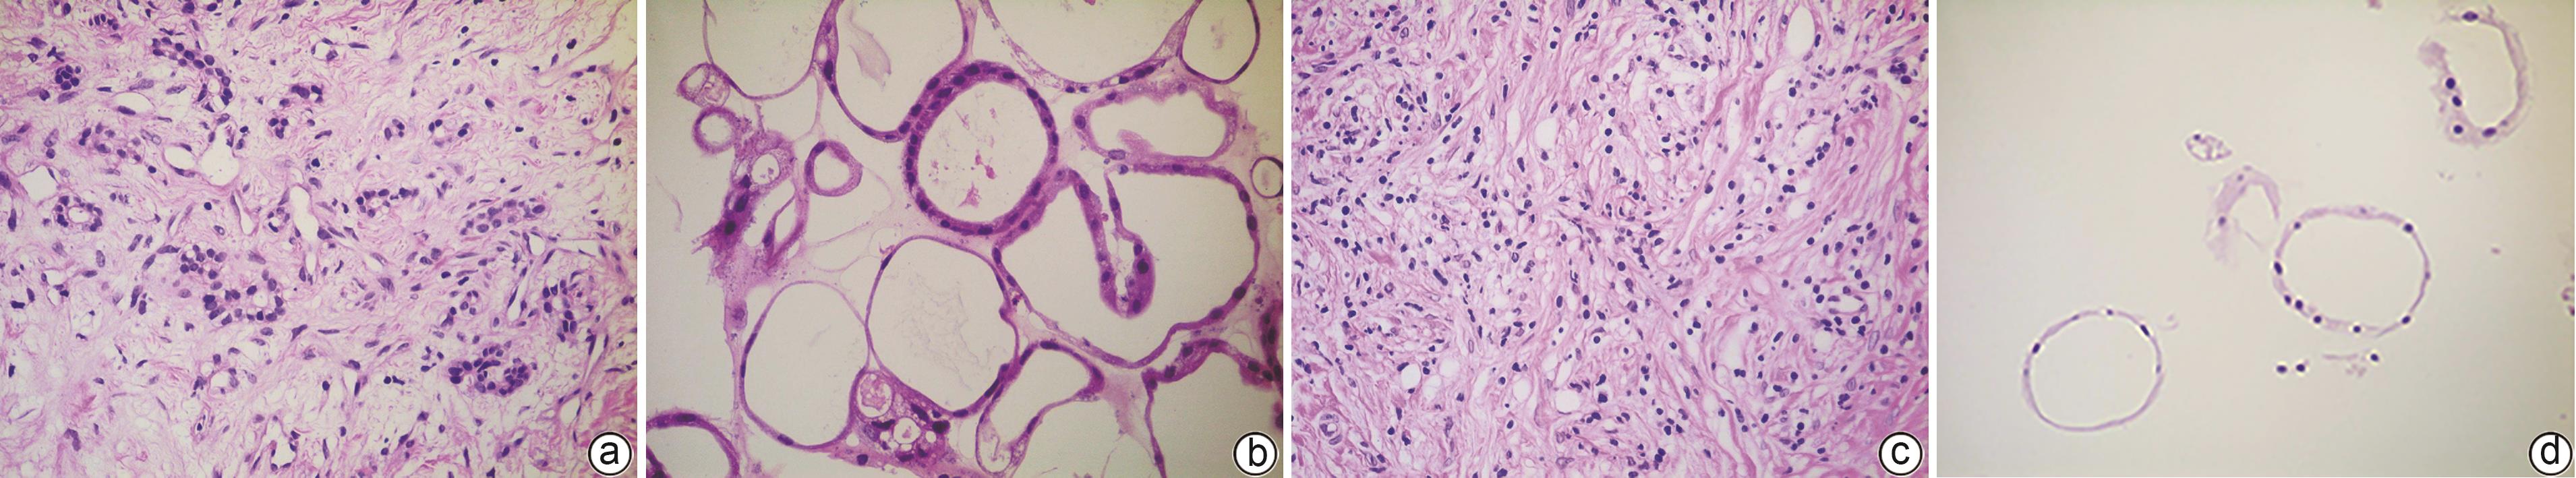

Construction of pancreatic cancer organoids and their sensitivity to chemotherapy drugs

Jingyu WANG, Rong HUANG, Yan LU, Ziran CHEN, Xiaojie ZHANG, Hu REN, Nan ZHANG, Dongbing ZHAO, Wei SONG, Xingguang ZHANG

2024, 40(9): 1853-1858. DOI: 10.12449/JCH240921

Abstract(1526) HTML (281) PDF (3800KB)(107)

Abstract:

Objective  To construct and identify a patient-derived organoid model, and to investigate the sensitivity of chemotherapy drugs using this model.  Methods  Pancreatic cancer cells were obtained from the surgical specimens of two female patients with a confirmed diagnosis of pancreatic cancer after tumor tissue digestion, and then the cells were inoculated into a culture dish using matrigel for three-dimensional culture. Paraffin sections were prepared for HE staining and immunohistochemical staining and were compared with the parent tumor tissue to determine whether the histopathological features of the tumor in vivo were preserved. The pancreatic cancer organoids were treated with seven chemotherapy drugs at different concentrations; Cell Titer-Glo®3D reagent was used to measure cell viability, and the results of drug sensitivity were analyzed.  Results  Two patient-derived pancreatic cancer organoids were successfully constructed, and HE staining and immunohistochemical staining showed that the pancreatic cancer organoids had consistent histopathological features with the tumors of the corresponding patient. Both pancreatic cancer organoids were more sensitive to gemcitabine monotherapy and the combination of oxaliplatin+SN38+fluorouracil, and patient 1 was more sensitive than patient 2. There were individual differences in the response to drugs between the organoids from different patients.  Conclusion  The pancreatic cancer organoid model successfully constructed in this study can reflect the histological classification of parent pancreatic tumors and can be used for in vitro chemotherapy drug sensitivity test, which is expected to provide a reference for clinical medication.